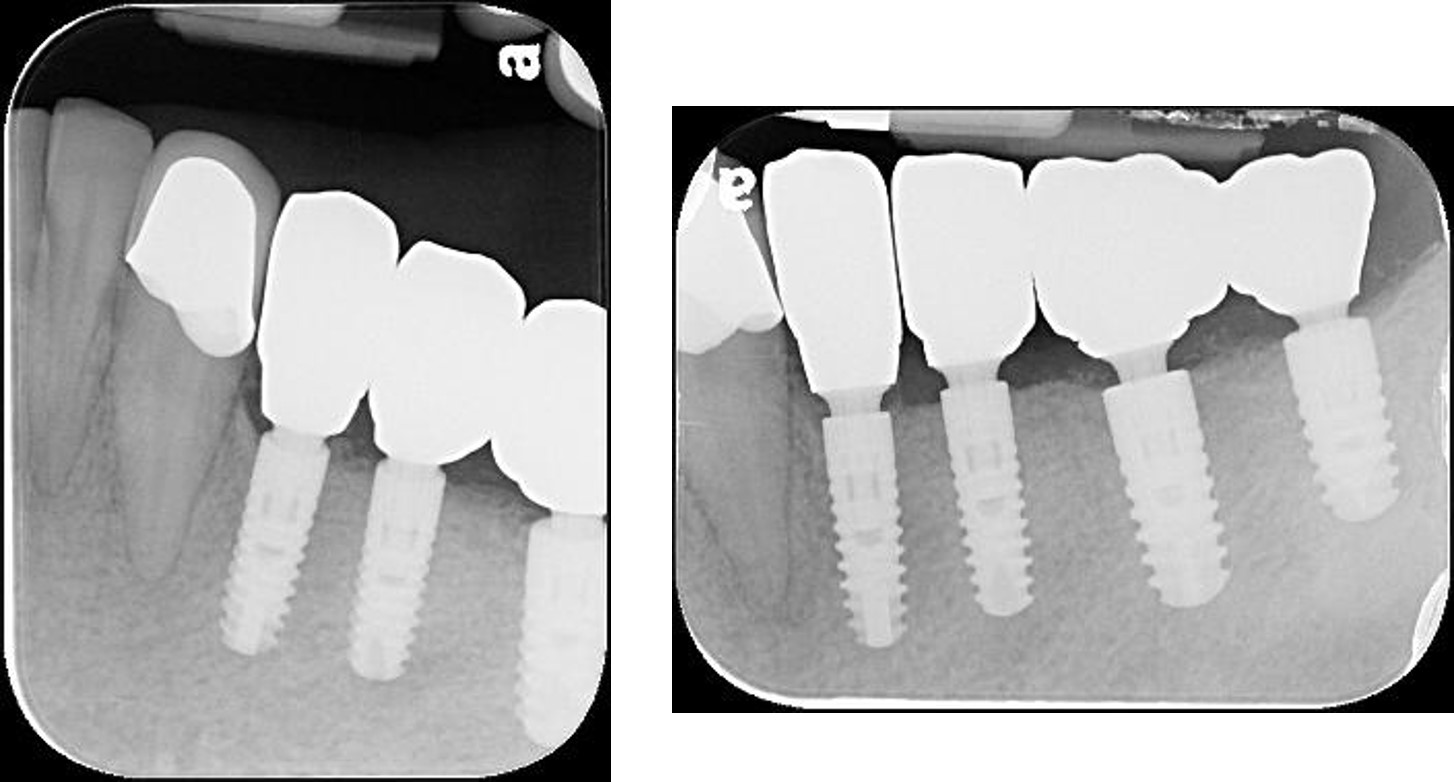

▲(治療前,左下骨高度足夠)

▲用X光看反而缺牙缺的更嚴重,看來我家人平常的口腔護理習慣的真的很差

▼植體植入後還要用X光確認,讓患者可以放心植牙有到位。

▼沒想到用X光看起來也挺牢靠的~~

治療前,左下骨高度足夠

植體植入後X光確認:#34-37

治療後X光:#33-37